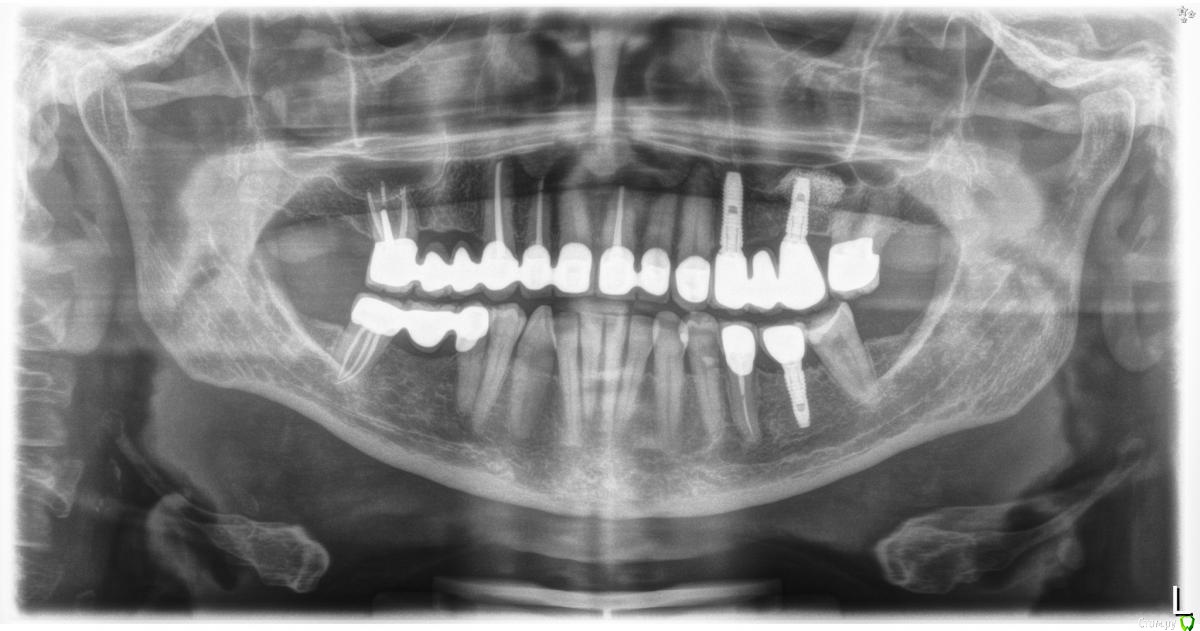

ellenchik Опубликовано 10 февраля, 2020 Автор Поделиться Опубликовано 10 февраля, 2020 wladdX , и снова Вам спасибо большое,что смотрите! КТ сделана в Германии. Может кто-то посмотрит срезы. А общий панорамный рентген был сделан в 2019 г. (ну хотя бы для сравнения с актуальными снимками КТ). А по этим скриншотам можно что-то сказать? Спасибо! Ссылка на комментарий